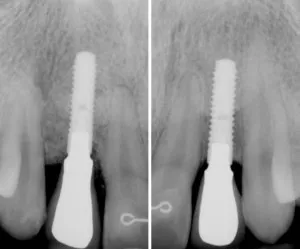

Antes: paciente con dos dientes frontales ausentes. 17 años después de colocación de implantes con injerto de encía